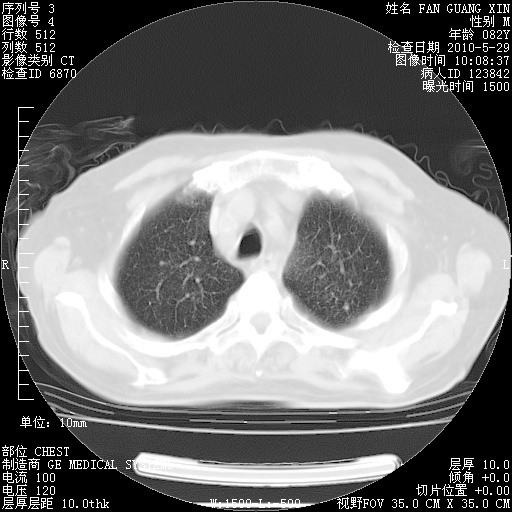

再治疗10天后的肺部CT

从白细胞总数和中性比例看好像合并感染。肺部纹理好像比上次多,支气管炎?其他感染?

阅读此次胸部CT,肺间质渗出性改变较入院时有吸收。目前从体温、白细胞、中性分叶明显增高,肯定存在细菌感染(发生医院感染哦,若无消化道及泌尿系统等感染的依据,肺部感染可能大)。若你院头孢哌酮舒巴坦钠耐药率较高,同意你的方案,若48小时体温仍高,可考虑使用碳青霉稀类抗菌药物,同时可予超声雾化、注意滴数时加大液体量。白蛋白33.30g/L较低哦,需加强营养等支持治疗。